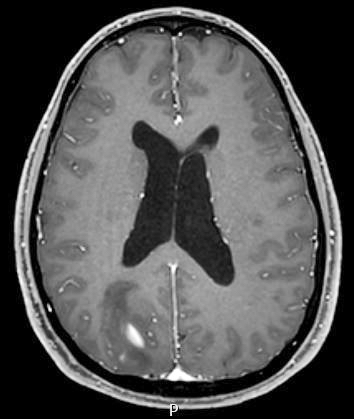

Radiology description

- CT:

- Expanding, intra-axial, poorly defined mass of low density

- Variable calcification may be seen

- Contrast enhancement and central hypodensity due to necrosis, occur with higher grades

- MRI:

- T1 hypodensity and T2 hyperintensity

- T2 hyperintensity with relative FLAIR sequence hypointensity (T2 FLAIR mismatch) is a relatively suggestive indication of IDH mutant astrocytoma (Clin Cancer Res 2017;23:6078)

- Distortion and enlargement of involved areas, including associated cortical ribbon

- Contrast enhancement is typically present in higher grade tumors (J Neurooncol 2019;141:327)

- Ring-like enhancement around central necrosis typical of grade 4

Radiology images